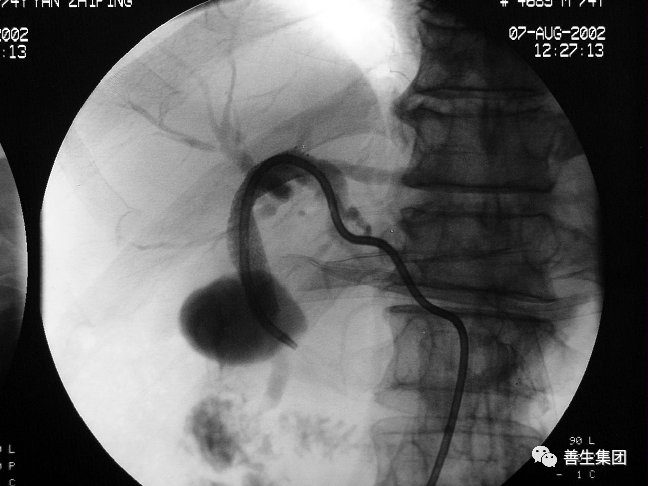

右肝MT,伴梗阻性黄疸。先穿刺右侧胆管,发觉左侧胆管更顺,改穿左侧。

胆管支架什么样子经皮肝胆管穿刺置管引流术(PTCD)及胆道内支架临床应用_https://www.jmylbn.com_新闻资讯_第23张

导管、导丝通过狭窄段

胆管支架什么样子经皮肝胆管穿刺置管引流术(PTCD)及胆道内支架临床应用_https://www.jmylbn.com_新闻资讯_第24张

金属内支架+局部狭窄扩张后

胆管支架什么样子经皮肝胆管穿刺置管引流术(PTCD)及胆道内支架临床应用_https://www.jmylbn.com_新闻资讯_第25张

金属内支架+引流管

胆管支架什么样子经皮肝胆管穿刺置管引流术(PTCD)及胆道内支架临床应用_https://www.jmylbn.com_新闻资讯_第26张